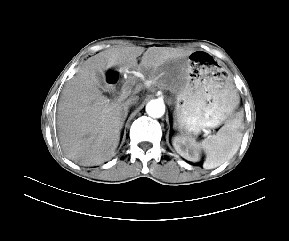

标题: CT19533:病变来源于哪?

患者,男,发现上腹部包块两月余。

病变位于肝胃间隙,实际就是位于小网膜囊(左肝下后间隙),呈轻度不均匀性强化,腹腔内及腹膜后见多发肿大淋巴结。所以我考虑肝胃间隙恶性胃肠间质瘤并淋巴结转移。

病灶强化不显著,灶周及腹膜后见多量淋巴结肿大,考虑淋巴瘤可能,其次考虑间质瘤

病灶与胰腺分界不清,来源于胰腺?

强化后病变与胃壁分界清楚,并且血供不是来源胃壁血管。考虑胰腺颈体癌并腹腔腹膜后淋巴结转移。